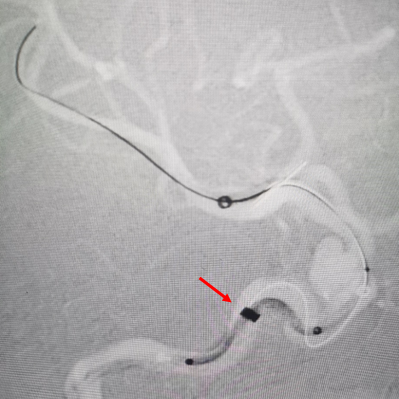

退支架外鞘管,将Surpass Streamline血流导向密网支架先释放到CAT5里6-7mm。

再退CAT5到外鞘管以下2mm,让支架锚定于远端。但发现支架远端定位过高,覆盖了脉前动脉,遂用CAT5回收支架,重新定位后释放。

动脉长鞘怎么置入术说·第十七期丨Infinity长鞘助力Surpass Streamline血流导向密网支架治疗双侧颈内迂曲路径动脉瘤一例_https://www.jmylbn.com_新闻资讯_第27张

由于血管迂曲,支架推出困难,遂进行远端减张释放,推出支架后再增张,因此导致支架远端打开不良,用3.5*15mm Gateway球囊在支架远端扩张。

球囊扩张后再进行导丝按摩支架,工作位造影显示支架贴壁有所改善,动脉瘤内造影剂滞留明显。